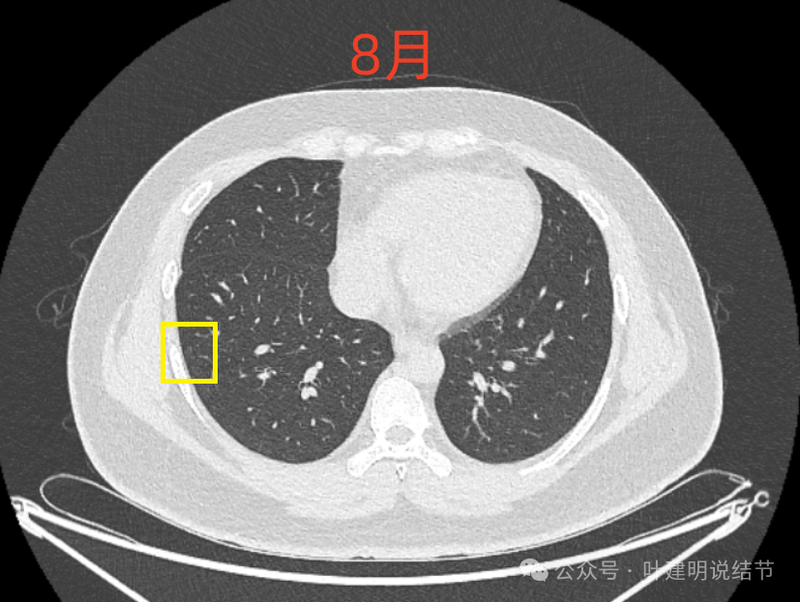

右肺尖磨玻璃结节,整体轮廓与边界清,有微小血管进入与穿行,但肿瘤本向说不上实性密度。

8月时似乎略模糊点,但显著的变化显然仍是说不上的。风险并不能算高,当然东西是肿瘤范畴的,原位癌或不典型增生均可能。

这样的对比,似乎略有变化,又似乎说不上明显变化。本身扫描条件也可能不同。所以我常强调,不要在意过于细微的变化,因为这不影响临床决策。而影响到决策的变化一眼就看出来了。有些同道呀,喜欢拿放大镜看,然后告诉患者有进展,很危险,得尽快手术!只能呵呵了。下面是不同指南与共识对于随访的建议,大家可以自己看。

现在的人工智能辅助诊断系统太过敏感,非常微小的结节都给你找出来,但是对于临床来说并没有多大意义。当结节才几个毫米的时候,既没有办法明确到底是什么,也没有必要明确到底是什么,按照中华医学会肺癌诊疗指南,8毫米以下纯磨玻璃结节或5毫米以下实性结节(包括混合密度结节实性成分不足5毫米)也就是年度复查就可以。所以其实并不一定要在意到底有多少处结节,或者要考虑是什么。主要就关注最主要的病灶,如果主病灶仍没有风险可以年度体检复查,那就可以随访,不能也不必有过大的思想顾虑。我看了你的CT,目前这些结节均风险小,其中右侧桔色框起来的是所谓主病灶,仍是纯磨密度,又还小,考虑不典型增生可能性较大;左下桔色的也是磨玻璃密度,但轮廓不如右上这处清楚,若确实肿瘤范畴,也是原位癌或不典型增生可能性大,但也有少许慢性炎伴肺泡上皮增生或纤维增生的可能性;中叶绿色的密度过高,更符合良性些;右下黄色的过小,11月份的像磨玻璃密度,边界较清,但对比8月时的,此灶不太明显,当然本身过小,也可能没有扫到最明显层面,不过总归风险小,能观察随访(左下的也8月时更显淡和不明显点)。总体上,这几处病灶都是风险还低,可以继续半年到一年复查随访,真若有明显进展并具有一定的风险再来干预处理不影响预后。本身年纪轻,又是多发结节,目前的病灶又都风险低,可以过于积极赶紧处理。意见供参考!